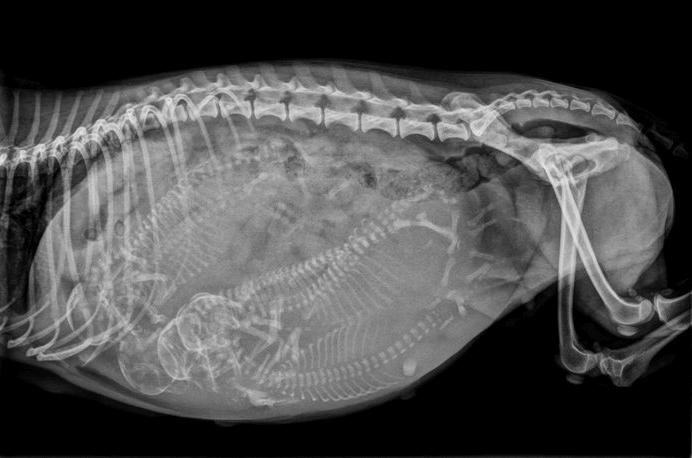

- 45天:怀孕第45天可以通过X光确定子宫里小汪的数量

- 55天:怀孕55天以后可以通过X光片初步确定是否能顺产